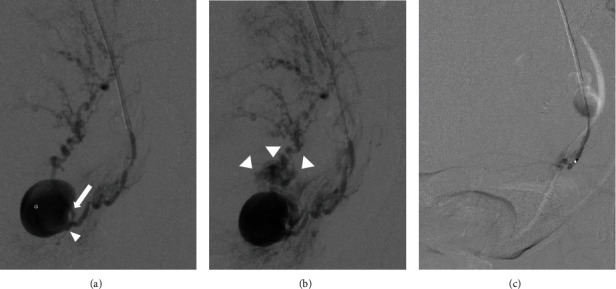

子宫动脉假性动脉瘤(UAP)是妊娠和产后危及生命的并发症。由于没有阴道出血,外生性UAP破裂的早期诊断是困难的。本研究报告了一例31岁的产后妇女,阴道分娩后7天出现腹痛和发烧,无产妇休克症状。超声检查显示外生性UAP破裂伴腹膜出血,经计算机断层扫描证实。介入放射学证实假性动脉瘤位于子宫动脉分叉处,诊断后立即用线圈和正丁-2-氰基丙烯酸酯栓塞。患者症状缓解,栓塞12天后出院。产后8个月,经阴道超声检查未见UAP。即使没有特定的危险因素,如剖宫产或子宫内膜异位症,外生性子宫内膜异位症也可能发生,而且子宫内膜异位症不一定在分娩后立即破裂。产科医生必须保持警惕外源性UAP破裂的可能性,表现为腹痛和产后发烧,而不是不稳定的生命体征。这是首次报道发生在子宫动脉分叉水平的外生性UAP。确定外生性UAP可能发生的部位有助于该病的早期诊断。

A uterine artery pseudoaneurysm (UAP) is a life-threatening complication during pregnancy and postpartum. Early diagnosis of exophytic UAP rupture is difficult due to the absence of vaginal bleeding. This study reports the case of a 31-year-old postpartum woman who presented with abdominal pain and fever seven days after vaginal delivery, without symptoms of maternal shock. Ultrasonography revealed a ruptured exophytic UAP with hemoperitoneum, which was confirmed using computed tomography. Interventional radiology confirmed that the site of the pseudoaneurysm was at the level of the uterine artery bifurcation, and embolization was performed immediately after diagnosis using a coil and n-butyl-2-cyanoacrylate. The patient's symptoms were relieved, and she was discharged 12 days after the embolization. At eight months postpartum, the UAP was not visible on transvaginal ultrasonography. Exophytic UAP can occur even in the absence of specific risk factors such as cesarean section or endometriosis, and the UAP may not necessarily rupture immediately after delivery. Obstetricians must remain aware of the possibility of exophytic UAP rupture manifesting as abdominal pain with postpartum fever, rather than as unstable vital signs. This is the first report of an exophytic UAP that occurred at the level of the uterine artery bifurcation. Identification of the sites where exophytic UAP can occur can aid in the early diagnosis of the condition.